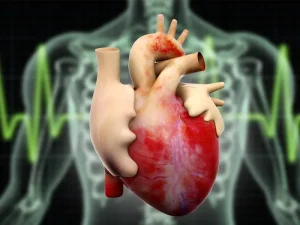

بزرگ شدن عضله قلب باعث مرگ میشود؟

بزرگی قلب به حالتی گفته می شود که عضله قلب به اندازه ای بزرگتر از حالت طبیعی خود می رسد. بر خلاف تصور افراد این

بزرگی قلب به حالتی گفته می شود که عضله قلب به اندازه ای بزرگتر از حالت طبیعی خود می رسد. بر خلاف تصور افراد این